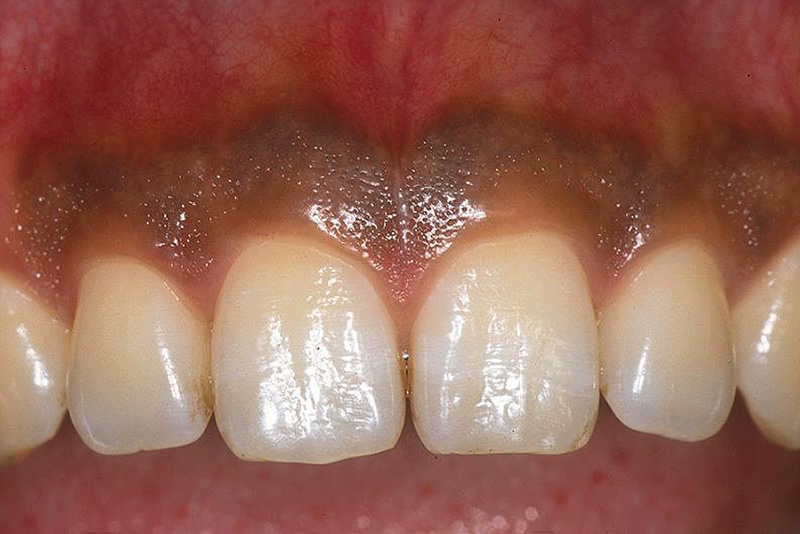

メラニン除去

| 上写真: | 術前の歯肉のメラニン沈着症。 |

| 下写真: | 局所麻酔下において注水下でのコンタクトチップを用いた接触照射により、黒褐色のメラニン沈着を含む上皮組織は効果的に削除されます。 術後の創傷治癒は早く良好で、通常は1週以内に上皮化し、2週間程度で正常歯肉に回復します。写真は4週後。 |

| 費 用: | 1歯あたり3,630円 顕微鏡加算6,050円 |

| リスク: | 過剰な出力や照射部へ注水スプレーが不足してしまった場合などの照射条件では、治癒の遅延や歯肉の退縮が生じることがあります。また、メラニンの除去が不完全で⼀部の残存が認められる場合には追加治療が必要となることがあります。 なお、顕微鏡を用いることで、より精度の高い治療が可能となります。 |